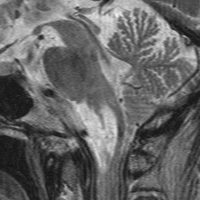

expanding, solid 固形腫瘍的なもの

壊死ではない「のう胞」を伴い,ガドリニウムで強く増強されます。グレード 4 (膠芽腫)と間違えるようなものです。しかし,のう胞はありますが中心壊死がありません。

腫瘍を大部分摘出できるので,積極的な摘出術をして,手術後には放射線化学療法を加えます。この例では,手術後の放射線治療計画の領域が狭ければ,60グレイを使用できる部位です。